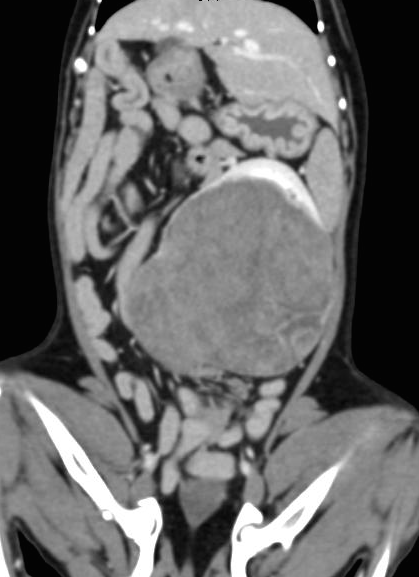

肝細胞癌と前立腺癌の併発した犬

肝臓腫瘍により腫大した肝臓と前立腺癌による尿道閉塞により膀胱の拡張を認める